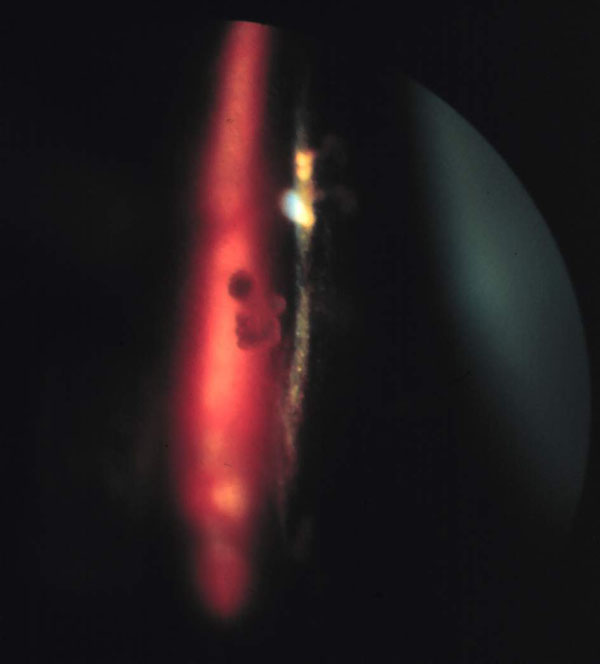

3. ábra Az üvegtesti tér elülső harmadát legjobban réslámpával, kiegészítő eszköz alkalmazása nélkül vizsgálhatjuk. A képen a cornea és a lencse reflexe mögött a mérsékelten elfolyódott üvegtest rostjai észlelhetők. A rostok között az elfolyósodott gél optikailag tiszta.